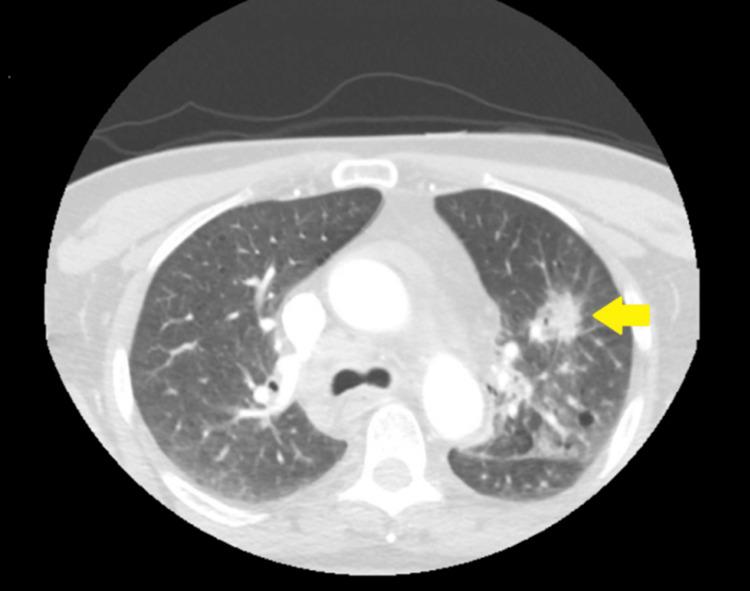

Endocarditis involves inflammation of the inner layer of the heart, known as the endocardium. This condition typically presents with vegetation, with bacteria and fungi usually being the primary culprits. It is divided into two main categories based on its cause: infectious endocarditis and noninfectious endocarditis (NIE). Most cases of NIE are associated with malignancies, most of which are adenocarcinomas of the pancreas and lungs. We present the case of a 63-year-old man with recently diagnosed stage 3 non-small cell lung cancer and a previous history of thrombosis to the renal and popliteal arteries alongside an extensive cardiovascular history who presented with blurry vision secondary to multiple acute ischemic strokes, initially thought to be a consequence of septic emboli due to bacterial endocarditis; however, further workup revealed otherwise, illustrating the complex relationship between malignancy and endocarditis and its ramification.

心内膜炎累及心脏内层,即心内膜的炎症。这种病症通常表现为赘生物,细菌和真菌通常是主要病因。根据病因,它主要分为两类:感染性心内膜炎和非感染性心内膜炎(NIE)。大多数NIE病例与恶性肿瘤相关,其中大多数是胰腺和肺部的腺癌。我们报告了一例63岁男性患者,最近被诊断为3期非小细胞肺癌,既往有肾动脉和腘动脉血栓形成史以及广泛的心血管病史,因多发性急性缺血性中风出现视力模糊,最初认为是细菌性心内膜炎导致的脓毒性栓子所致;然而,进一步检查结果并非如此,这说明了恶性肿瘤与心内膜炎之间的复杂关系及其后果。